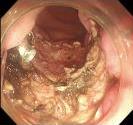

• 电子胃镜联合实验室指标检测在胃癌诊断中的价值及其与临床病理特征的关系

2025, 31(12):49-55. DOI: 10.12235/E20240712

摘要 (65) HTML (26) PDF 718.76 K (63) 评论 (0) 收藏

摘要:目的 探究电子胃镜联合实验室指标[血清糖类抗原724(CA724)、糖类抗原19-9(CA19-9)、微RNA-183(miRNA-183)和微RNA-144(miRNA-144)]检测在胃癌诊断中的价值及其与临床病理特征的关系。方法 选取2022年12月-2023年12月经病理检查确诊的122例胃癌患者作为A组(2022年12月-2023年12月该院收治),纳入该院同期收治的130例胃部良性肿瘤患者作为B组。所有患者在病理检查确诊前均先行电子胃镜检查,比较两组患者电子胃镜检查阳性率、血清CA724、CA19-9、miRNA-183和miRNA-144水平,并分析其对胃癌的诊断价值,比较不同病理特征胃癌患者电子胃镜检查阳性率及血清指标水平。结果 A组电子胃镜检查阳性率、血清CA724、CA19-9和miRNA-183水平高于B组,血清miRNA-144水平低于B组,差异均有统计学意义(P < 0.05)。与单独诊断相比,五者联合诊断胃癌的曲线下面积(AUC)更高,差异有统计学意义(P < 0.05)。不同分化程度、淋巴结转移情况和TNM分期患者电子胃镜检查阳性率、血清CA724、CA19-9、miRNA-183和miRNA-144水平比较,差异均有统计学意义(P < 0.05)。结论 电子胃镜检查在诊断胃癌及评估其病理特征方面,具有较好的应用效果,相关实验室指标(血清CA724、CA19-9、miRNA-183和miRNA-144)与胃癌的发生及病理特征密切相关,五者联合检测,可提高对胃癌的诊断效能。